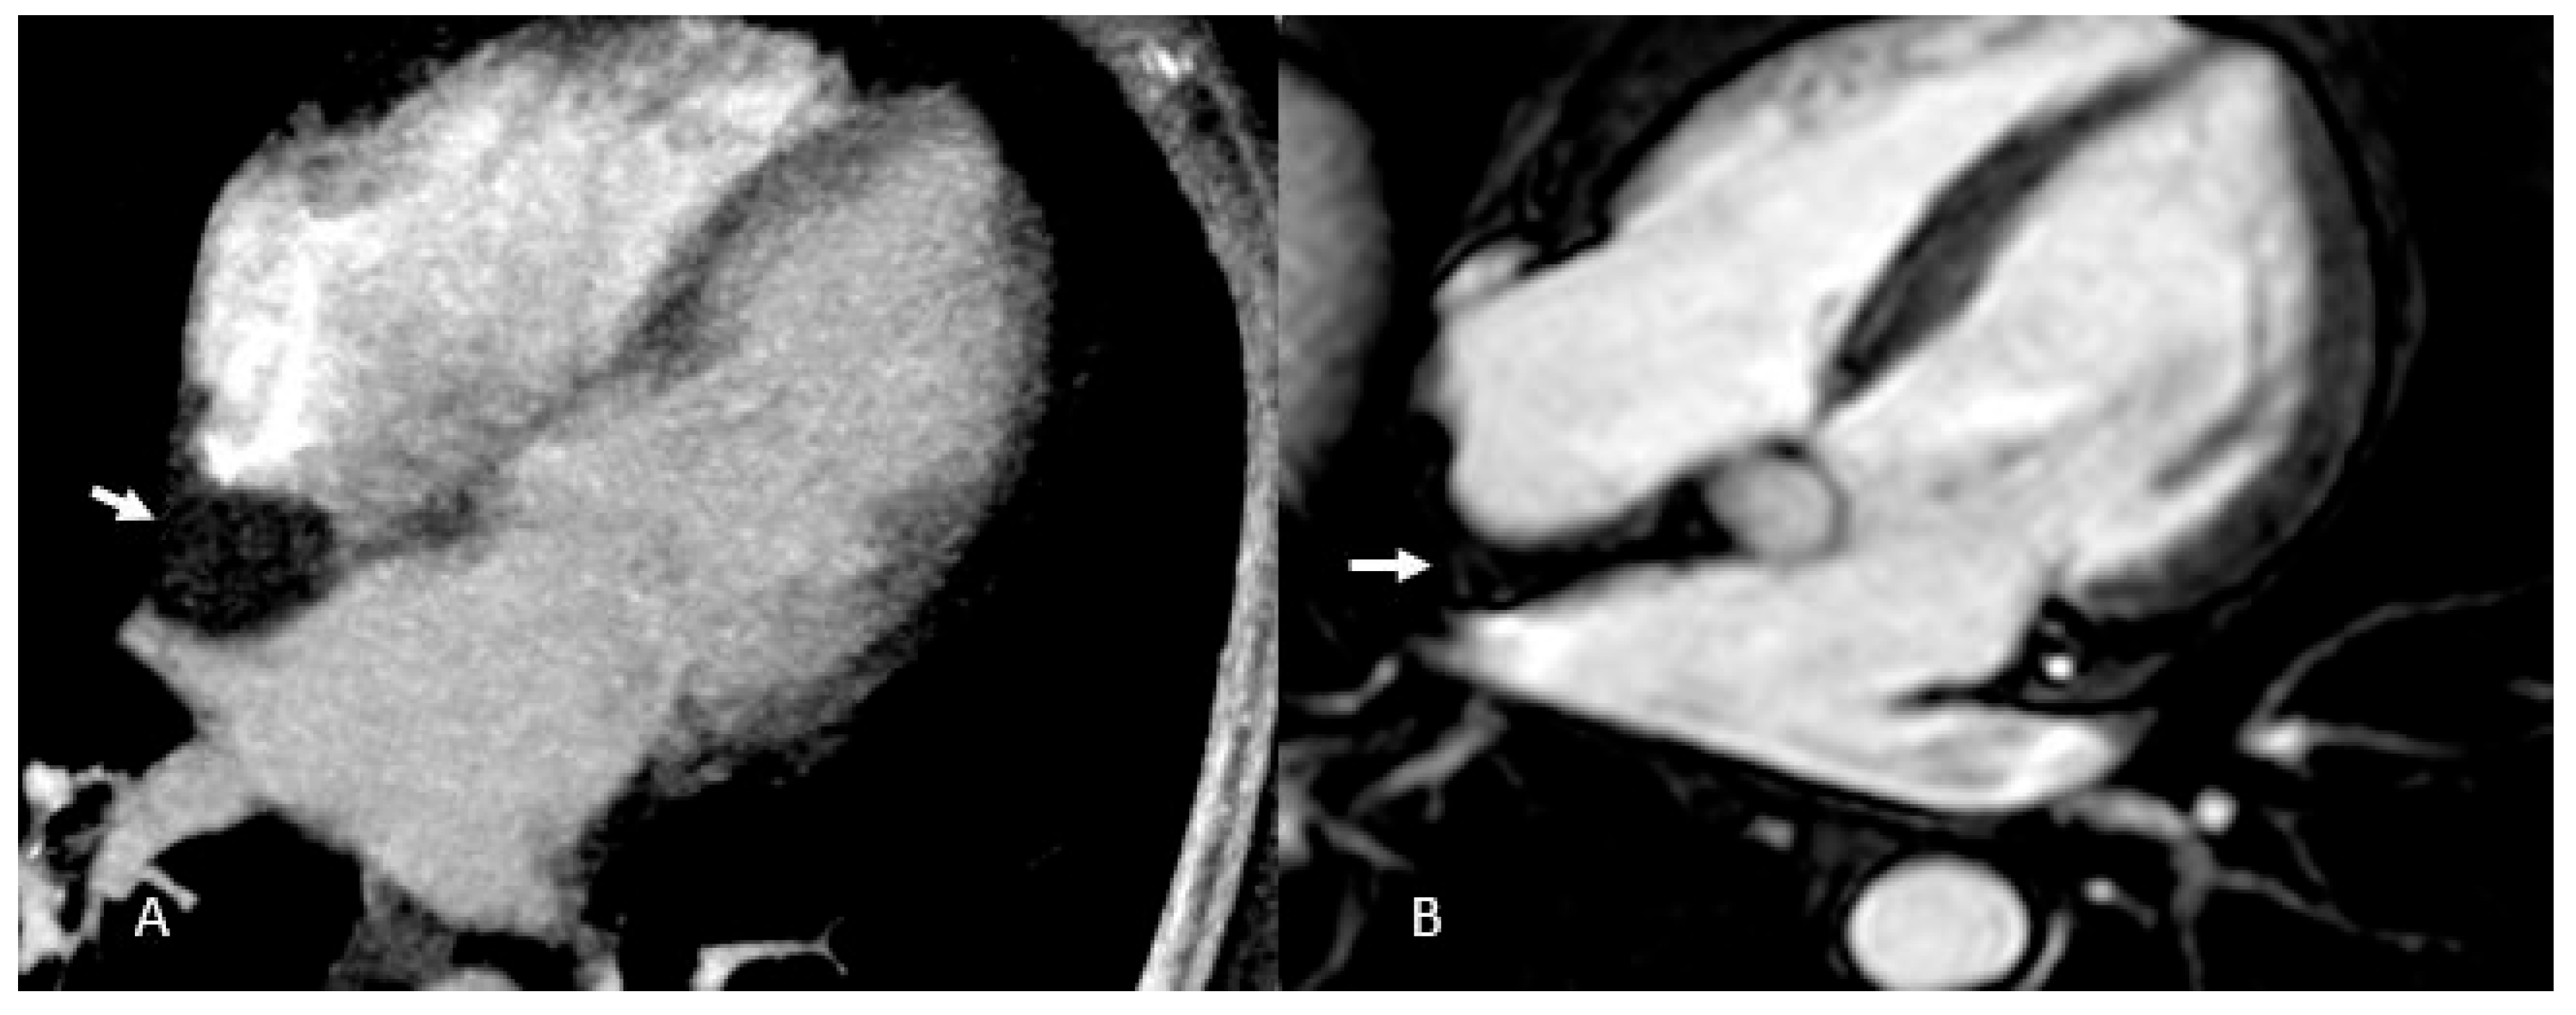

Figure 3. Thrombus (white arrows). CINE (A), EGE (B), and LGE (C) sequences show a large thrombus (arrows) at the apex of the left ventricle. Note that it remains hypointense and does not take up contrast, which is typical of thrombi and helps in distinguishing them from other cardiac masses.

Thrombi reveal themselves as non-opacified (“vacuum”) areas after contrast injection (Figure 3)—critical to recognize for proper treatment—and are classically found in the left atrium of patients with atrial fibrillation. On CT they appear as hypodense, non-enhancing lesions [29]; on MRI their signal shifts with age: acute clots display intermediate intensity on both T1 and T2 (due to oxyhemoglobin), subacute thrombi become T1-dark and T2-bright as hemoglobin converts to methemoglobin and draws in water, and chronic, fibrosed clots lose water, appear dark on both T1 and T2, and generally lack contrast uptake (though longstanding fibrotic thrombi can show rim enhancement on delayed sequences), similar to normal fibrotic tissue [2,3,12,30].